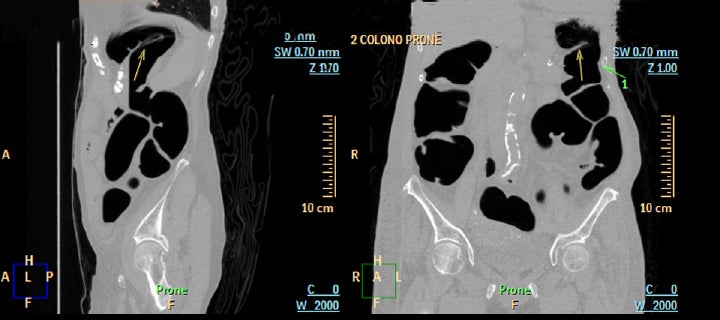

Ct Colonography Ct Scan Colon Axial Stock Illustration 1245896428 ...